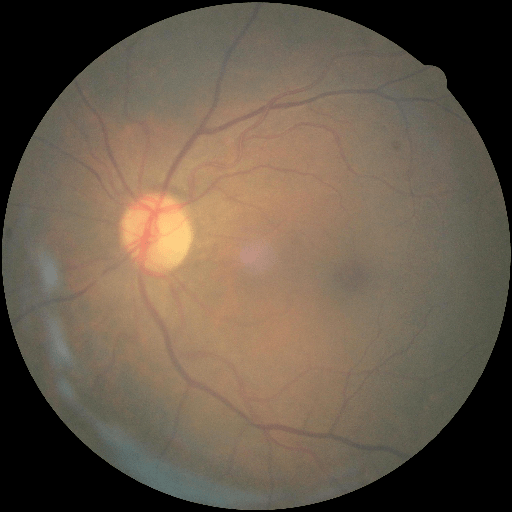

We conducted a case study on diagnosing diabetic retinopathy with ensembles of DL models. For benchmarking the performance of our ensemble-based solutions under the scheme described in Sec.3.3, we used two popular collections of diabetic retinopathy image data, the Kaggle Diabetic Retinopathy dataset [22] (hereafter referred to as “Kaggle-DR”) and the Messidor-2 dataset [23], each respectively consisting of and high resolution images. Diabetic retinopathy is graded into five SLs, as displayed in Figure 2. Following the problem setup used in previous papers [24], we trained models to distinguish the referable (SL2-4) cases from the non-referable ones (SL0 & SL1) (see Section B.1 for more detailed descriptions). We also tested our trained ensemble models on two o.o.d. image datasets (ImageNet [25] and CIFAR-10 [26]) to examine their capabilities of identifying o.o.d. inputs (see Section B in the supplementary materials).

The Kaggle-DR dataset comprises high resolution images. The presence of diabetic retinopathy is rated into five different SLs: no-DR (SL0), mild (SL1), moderate (SL2), severe (SL3), and proliferate (SL4), as illustrated in Figure 2. We divided the Kaggle-DR dataset into a development set and a test set, which respectively consisted of and images. The data in the development set were used to train and validate our Deep Learning (DL) models. The Messidor-2 dataset [38] that consisted of images was also used in our experiment as an additional dataset to test the true generalization performance of the models trained on the Kaggle-DR dataset. Images in Messidor-2 dataset were graded into the five SLs as in the Kaggle-DR dataset. Figure S.1 provides an illustration of the datasets used in our experiments.

The image data used in our experiment were all unified into square-shaped images with resolutions or in our preprocessing procedures. For training each neural network model, only images of the same resolution were used. The original images came with either of the two forms as exemplified in Figure S.2. In the first form (Figure 2(a)), the entire fundus was visible in the image. We cropped the image such that the fundus was tightly fitted inside the square. In the second form of input images shown in Figure 2(b), part of the fundus was not visible. We padded blank strips to make the image square-shaped and in a unified resolution. See the provided code for further details.